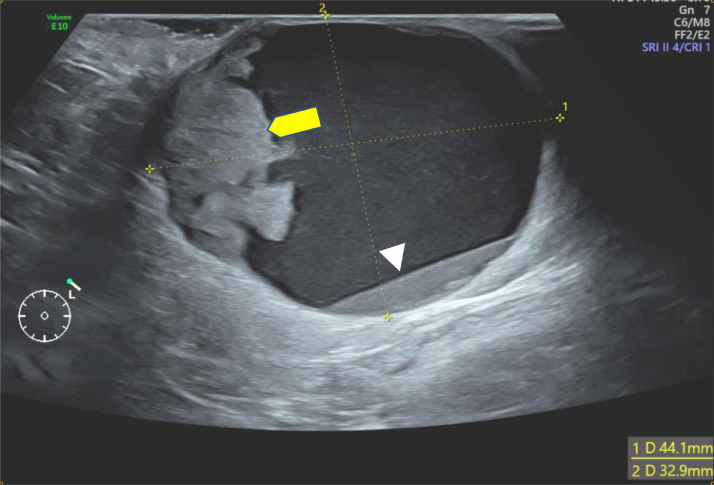

Ultrasonography was first performed showing a supernumerary breast tissue, of left axillary location, with a complex cystic mass containing an echogenic-anechoic liquid level, and a tissue component, that appears hyperechoic, with ill-defined margins, homogeneous (Fig. 2), with vascular pedicle in color Doppler (Fig. 3) and hard elasticity in ultrasound elastography (Fig. 4).

Fig. 2.

Ultrasound of the left axilla showing a complex cystic and solid mass, containing an echogenic-anechoic liquid level (head arrow), and a tissue component (yellow arrow).